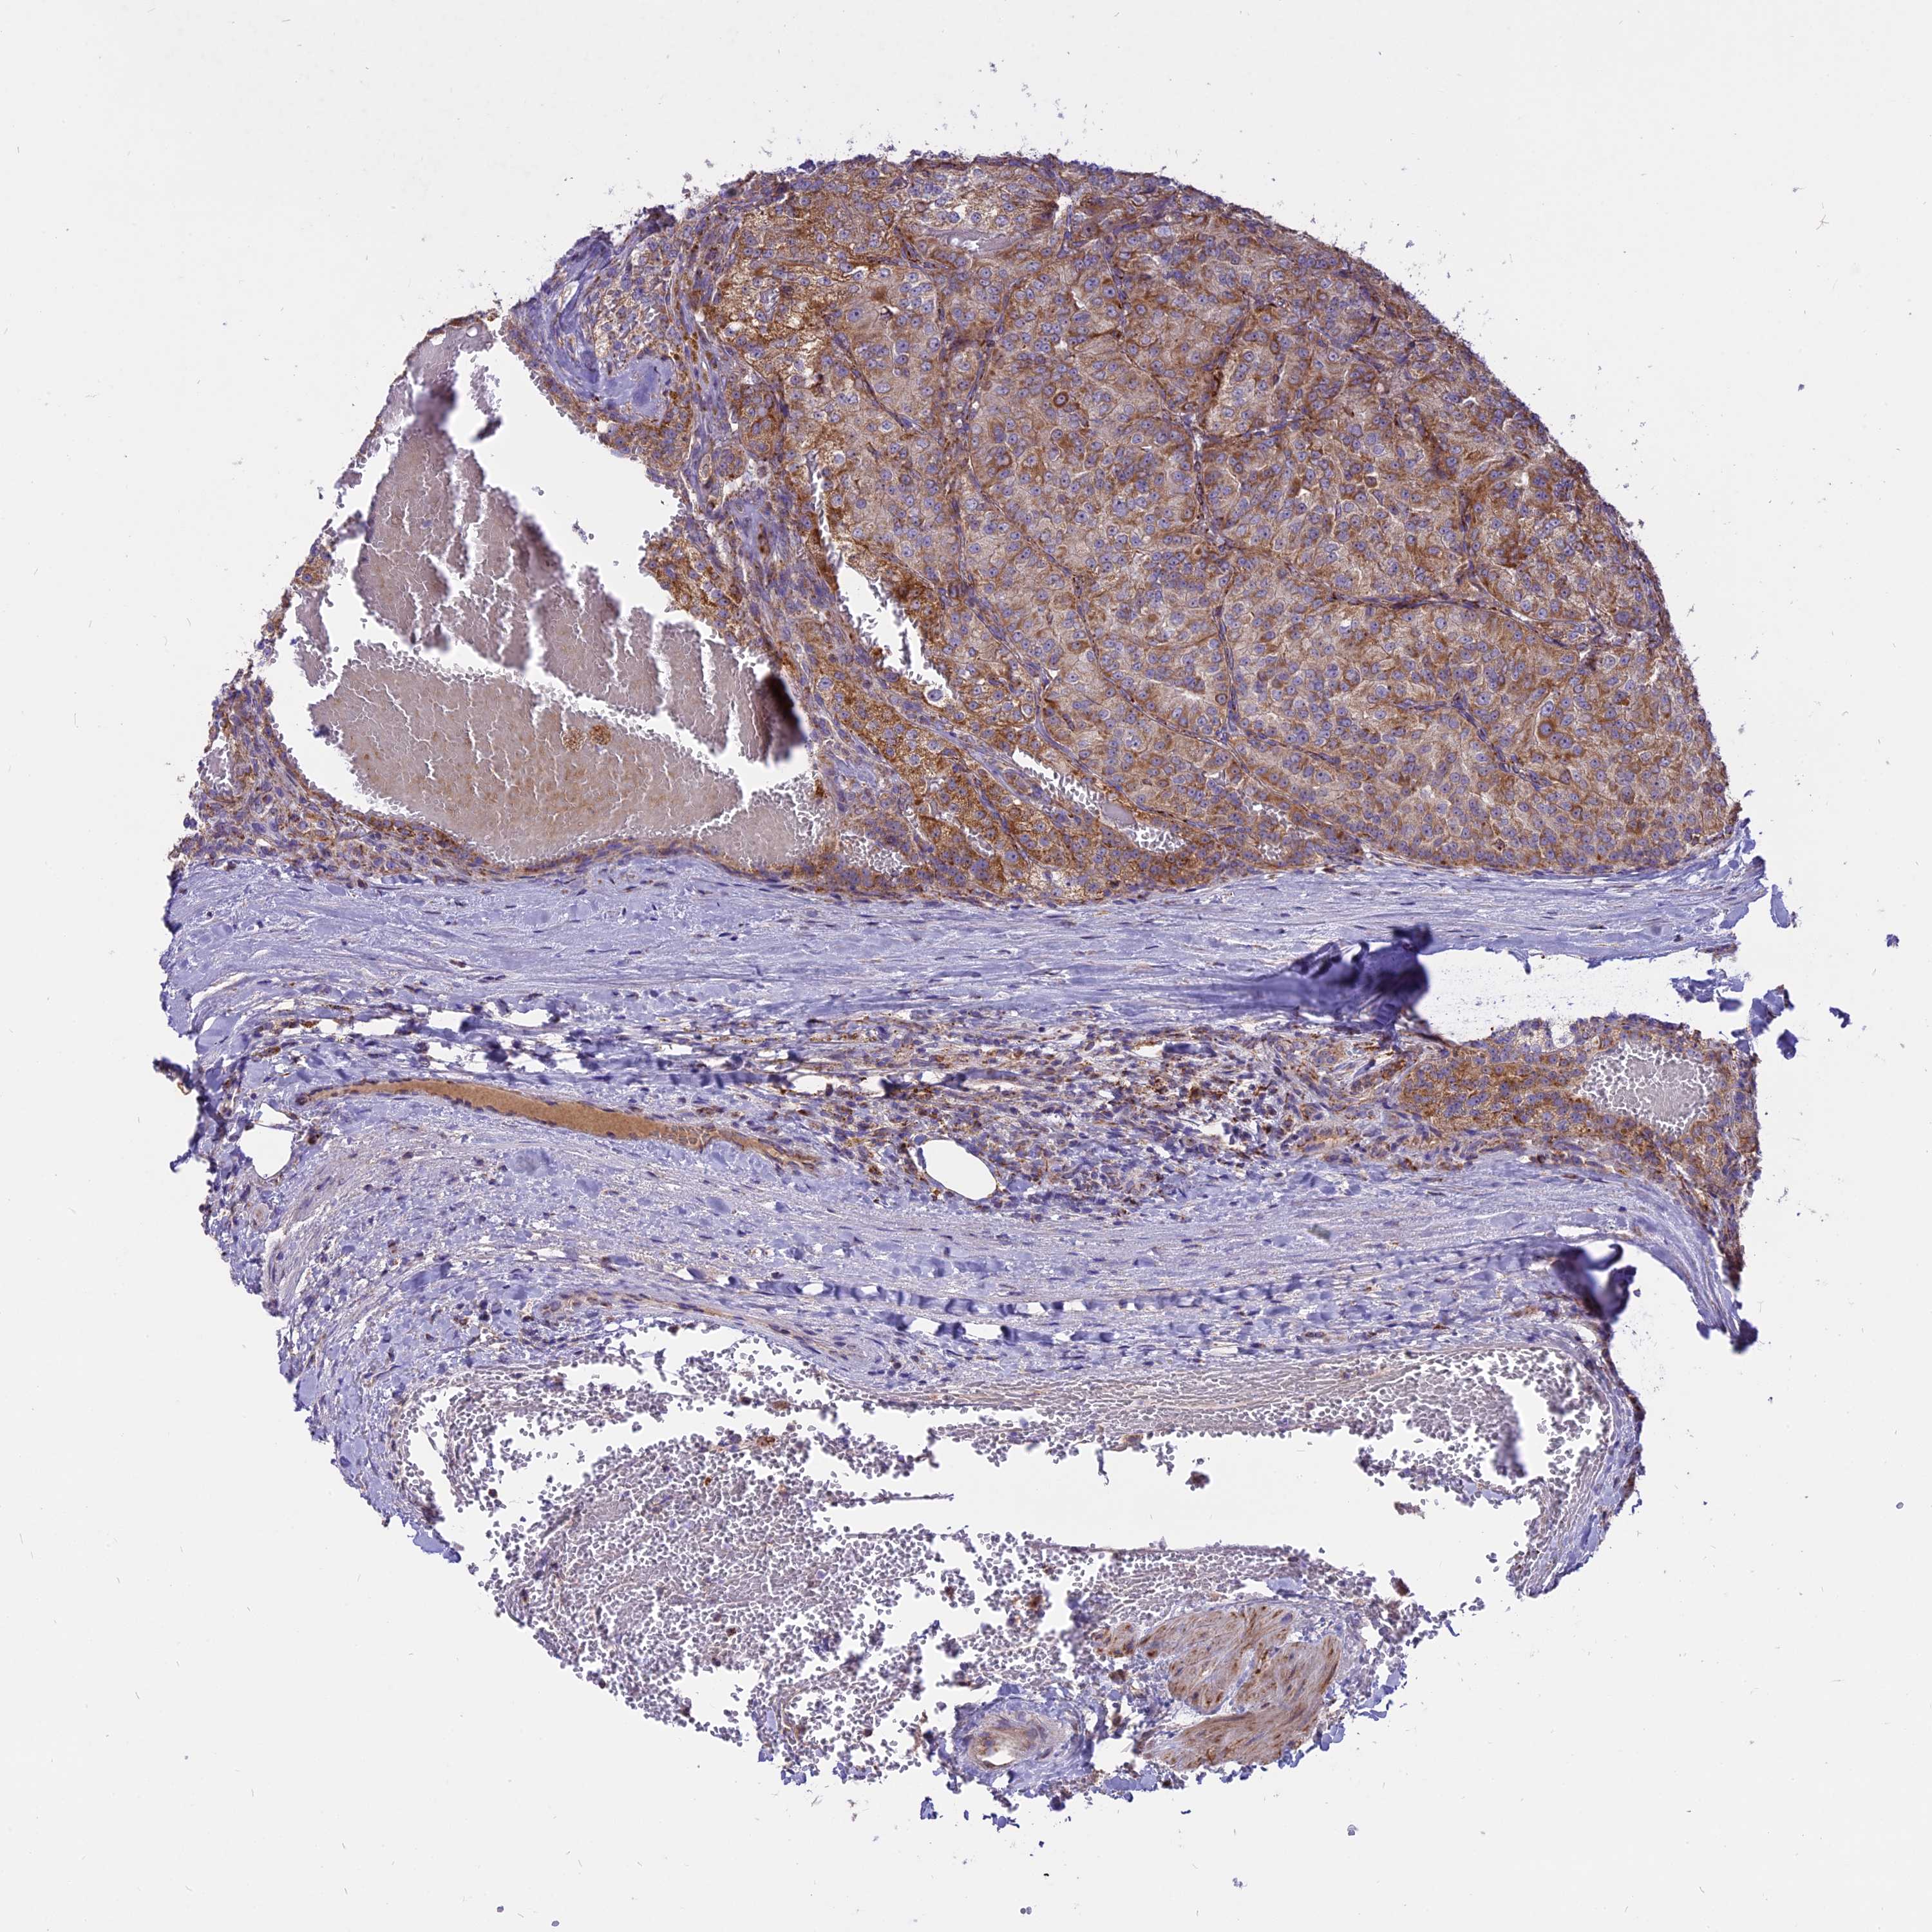

KIDNEY RENAL CLEAR CELL CARCINOMA (TCGA) - Interactive survival scatter ploti

The Survival Scatter plot shows the clinical status (i.e. dead or alive) for all individuals in the patient cohort, based on the same data that underlies the corresponding Kaplan-Meier plots. Patients that are alive at last time for follow-up are shown in blue and patients who have died during the study are shown in red.

The x-axis shows the expression levels (FPKM) of the investigated gene in the tumor tissue at the time of diagnosis. The y-axis shows the follow-up time after diagnosis (years). Both axes are complimented with kernel density curves demonstrating the data density over the axes. The top density plot shows the expression levels (FPKM) distribution among dead (red) and alive patients (blue). The right density plot shows the data density of the survived years of dead patients with high and low expression levels respectively, stratified using the cutoff indicated by the vertical dashed line through the Survival Scatter plot. This cutoff is automatically defined based on the FPKM cutoff that minimizes the p-score. The cutoff can be changed by dragging the vertical line or by entering a cutoff value in the square labeled "Current cut-off".

Under the Survival Scatter plot the p-score landscape (black curve; left axis) is shown together with dead median separation (red curve; right axis). Dead median separation is the difference in median mRNA expression between patients who have died with high and low expression, respectively. It is calculated as follows: median FPKM expression of dead patients with high expression - median FPKM expression of dead patients with low expression. This is intended to aid the user in visually exploring custom cutoffs and the associated p-scores and dead median separation.

Individual patient data is displayed and can be filtered by clicking on one or more of the category buttons on the top of the page. Categories describing expression level and patient information include: high, low, alive, dead, female, male and tumor stages. The scale of the x-axis can be toggled between linear and log-scale by clicking on the "x log" button. Mouse-over function shows TCGA ID, patient information and mRNA expression (FPKM) for each patient.

& Survival analysisi

Kaplan-Meier plots summarize results from analysis of correlation between mRNA expression level and patient survival. Patients were divided based on level of expression into one of the two groups "low" (under cut off) or "high" (over cut off). X-axis shows time for survival (years) and y-axis shows the probability of survival, where 1.0 corresponds to 100 percent.

COX17 is not prognostic in Kidney Renal Clear Cell Carcinoma (TCGA)

Best expression cut offi

Based on the FPKM value of each gene, patients were classified into two groups and association between prognosis (survival) and gene expression (FPKM) was examined. The best expression cut-off refers the FPKM value that yields maximal difference with regard to survival between the two groups at the lowest log-rank P-value. Best expression cut-off was selected based on survival analysis .

When clicking on this number, the vertical dashed line indicating cut-off, the interactive survival plot, and the Kaplan-Meier curve will be adjusted to show results based on the best expression cut-off.

: 138.5

Median expressioni

Median expression refers to the median FPKM value calculated based on the gene expression (FPKM) data from all patients in this dataset. When clicking on this number, the vertical dashed line indicating cut-off, the interactive survival plot, and the Kaplan-Meier curve will be adjusted to show results based on the median expression.

: N/A

Median follow up timei

Median follow up time refers to the median time (years) after diagnosis with this type of cancer, based on clinical data from all patients in this dataset.

P scorei

Log-rank P value for Kaplan-Meier plot showing results from analysis of correlation between mRNA expression level and patient survival.

N/A

5-year survival highi

5-year survival for patients with higher expression than the expression cutoff.

For melanoma and glioma, 3-year survival is shown.

5-year survival lowi

5-year survival for patients with lower expression than the expression cutoff.

TCGA RNA samplesi

RNA-seq data is reported as average FPKM (number Fragments Per Kilobase of exon per Million reads), generated by the The Cancer Genome Atlas (TCGA) .

Normal distribution across the dataset is visualized with box plots, shown as median and 25th and 75th percentiles. Points are displayed as outliers if they are above or below 1.5 times the interquartile range. FPKM values of the individual samples are presented next to the box plot.

Average pTPM 143.6

Number of samples 521